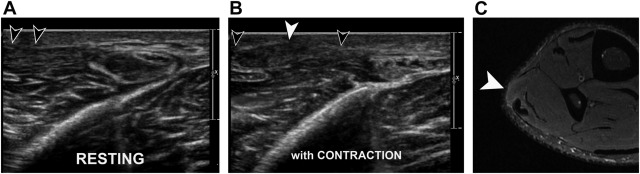

Sonography of Morton's neuromas.

AJR Am J Roentgenol. 174: 1723-1728Torriani M. Kattapuram S.V.

Technical innovation. Dynamic sonography of the forefoot: the sonographic Mulder sign.